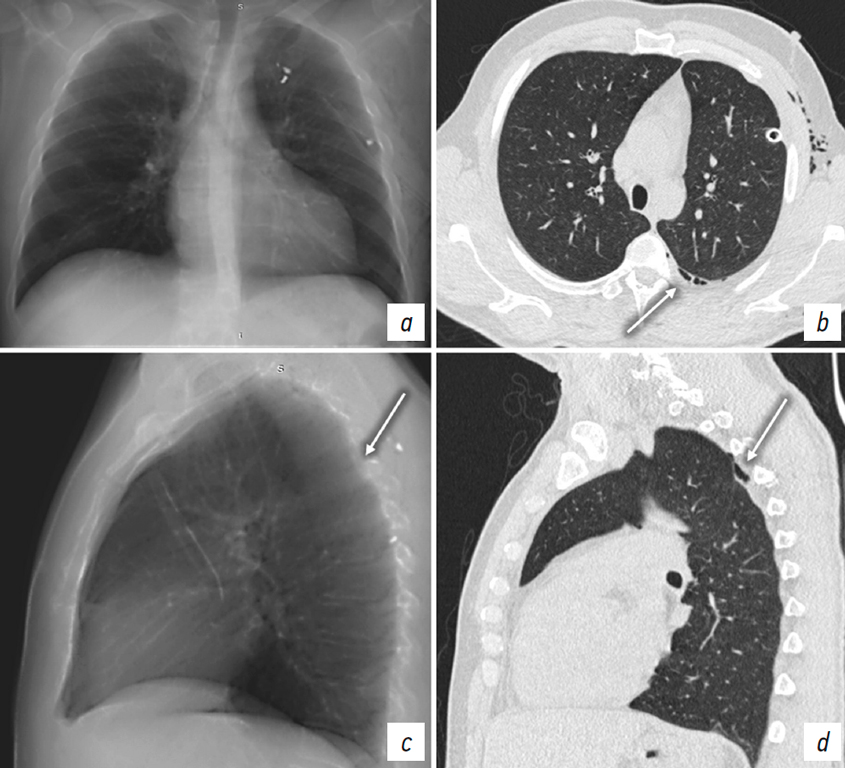

In all eight false-positive cases of pneumothorax, specific CT features were identified. A thin collection of air was noted between the inner surface of the thoracic cage and lungs, predominantly in the mid- and basal zones, with a heterogeneous structure caused by multiple septations of varying thickness and morphology and areas of fat density (–100 to –80 HU). These findings were consistent with subcutaneous emphysema but with an atypical location, within the thoracic cavity projection. On radiograph, the patients exhibited a well-defined radiolucent band between the chest wall and lung margin (Fig. 3).

Fig. 3. Patient M. a, chest X-ray in the anteroposterior view. Chest CT: b, coronal plane; c, d, axial plane at different levels. Pneumomediastinum. Extrapleural emphysema on the right (arrows).

Рис. 3. Пациент М. a — рентгенограмма органов груди в прямой проекции. КТ органов груди: b — фронтальная плоскость; c, d — аксиальная плоскость на разных уровнях. Пневмомедиастинум. Эмфизема ЭПП справа (стрелки).